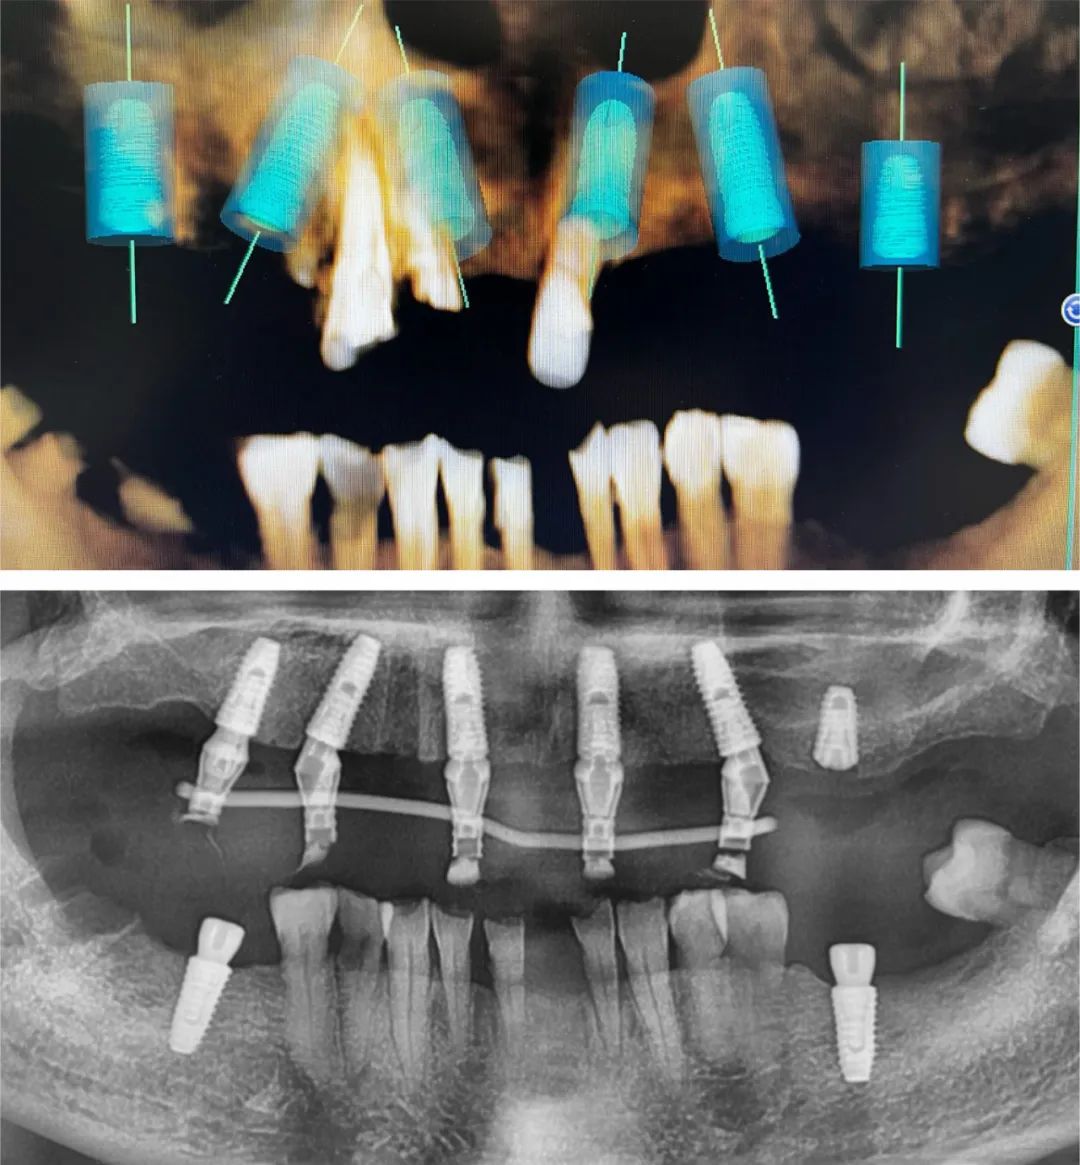

2017年,张嘉宇开始尝试数字化种植。彼时,口腔种植技术已在国内逐步普及,但数字化对于大多数种植医生来说还是一个陌生的领域。

“数字化种植包括数字化口腔扫描、数字化种植方案设计和数字化导板导航手术等几个环节,它比传统的人工取模更精准、更舒适,手术不需要翻瓣,创伤小,是对现有种植技术的一个有益的补充。”

基于对常规种植和数字化种植的丰富临床经验,张嘉宇认为后者当然有其相应的优势,但任何技术都只是达成治疗目标的一个工具。工欲善其事,必先利其器,但不要为器所累,数字化种植和传统种植殊途同归,各有优势,需要合理选择。

“单颗或几颗牙齿缺失时,口腔里还有足够多的牙来固定导板,采用数字化导板导航进行种植还是比较精准的,但如果缺的牙比较多,导板的固定只能采用牙和口腔黏膜的混合支持式,因为牙和黏膜的强度、弹性是不一样的,可能会影响到导板的稳定性,从而影响种植的精准度。另外,导板的硬度也会影响到种植效果。”

张嘉宇认为,复杂的种植病例和需要种植位置极度精确的,差误不能超过0.5毫米的病例,数字化导板导航种植是一个不错的选择。

“我每一台手术之前都要分析到位,不打无准备之仗。因为之前机构的手术室没有显示屏,手术时看不到患者的CBCT,只能凭着记忆和肉眼观察去做,对于难度较大的案例,我都会在术前把模拟植入的位置摆好,存在手机里反复熟悉,做到心中有数。”